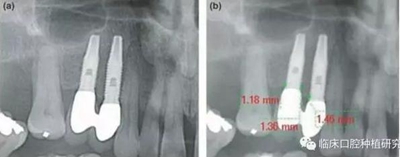

因而,該研究對(duì)隨訪(fǎng)達(dá)5年以上的牙列缺損種植修復(fù)患者,進(jìn)行了觀察性縱向回顧性研究。通過(guò)影像學(xué)資料對(duì)比種植體周?chē)俏蘸脱乐芄俏?,?duì)其潛在危險(xiǎn)因素,如修復(fù)體設(shè)計(jì)、口腔衛(wèi)生、植體規(guī)格也進(jìn)行了研究。單變量統(tǒng)計(jì)分析結(jié)果發(fā)現(xiàn),性別、種植體系統(tǒng)、拔牙原因、聯(lián)冠修復(fù)、種植體平臺(tái)和修復(fù)體間水平距離與種植體周?chē)俏沼酗@著相關(guān)性。多變量統(tǒng)計(jì)分析結(jié)果發(fā)現(xiàn),性別、種植體系統(tǒng)、拔牙原因、聯(lián)冠修復(fù)、種植體平臺(tái)和修復(fù)體間水平距離與種植體周?chē)俏胀瑯泳哂酗@著相關(guān)性。其結(jié)果認(rèn)為種植體平臺(tái)和修復(fù)體間水平距離對(duì)種植體周?chē)俏肇?fù)向影響最大,且這一距離適宜在3.3 mm-6 mm。若超出此范圍,則對(duì)種植體周骨吸收不再有影響,但外展隙會(huì)逐漸增大,菌斑堆積增多。